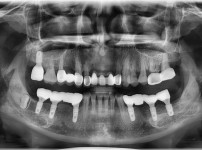

전체임플란트

임플란트